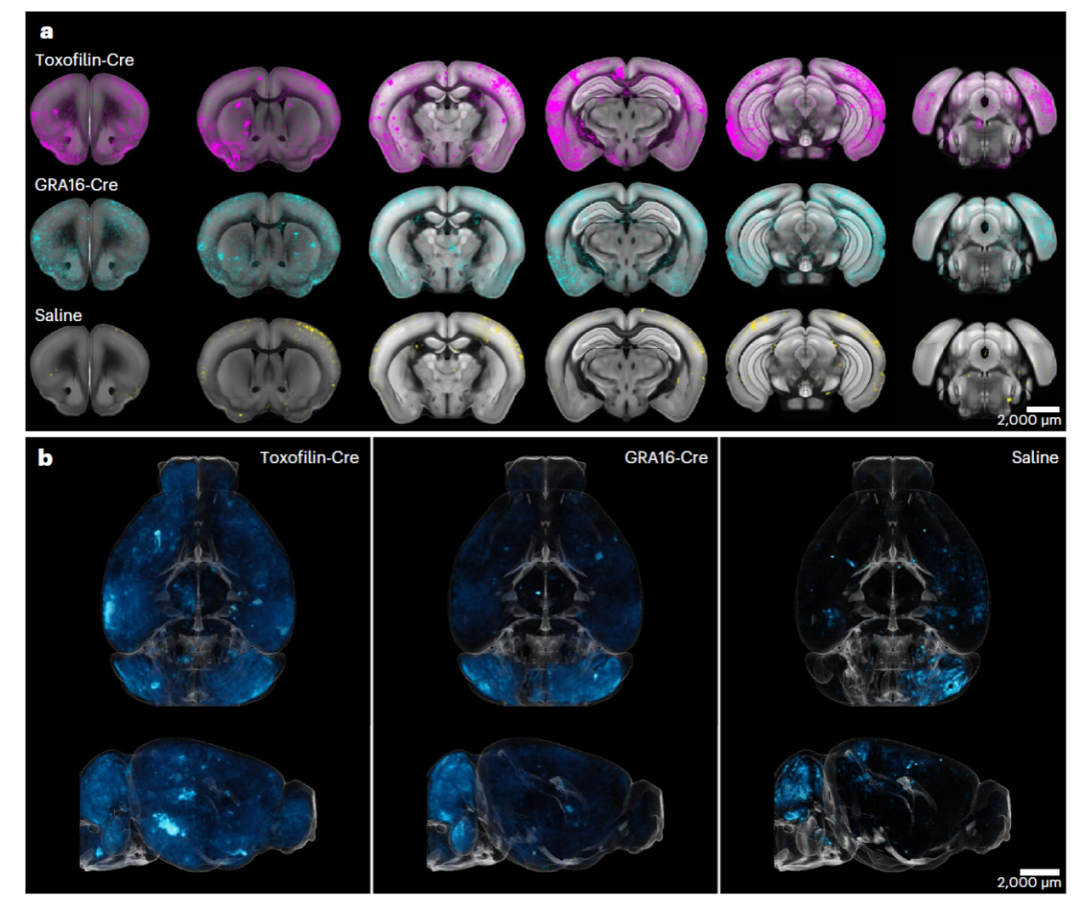

图片

图4 3D 图像展示弓形虫(荧光标记)进入小鼠大脑细胞中(图片来源:参考文献 3)